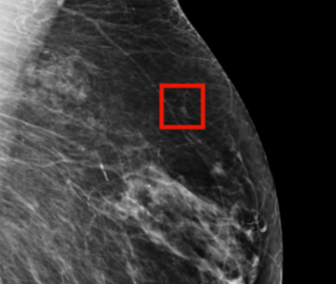

유방암의 조기 발견은 생존율 향상에 중요한 요소입니다. 정기적인 유방자가검진과 더불어, 유방 X선 촬영(맘모그래피)은 유방암 조기 진단에 있어서 핵심적인 역할을 합니다. 최신 지침에 따라 여성들은 특정 연령부터 정기적으로 맘모그래피 검사를 받는 것이 권장됩니다. 또한, 유전적 소인이 있는 여성의 경우, 유전 상담과 함께 추가적인 스크리닝이 필요할 수 있습니다. 생활 습관의 변화도 유방암 예방에 중요한데, 균형 잡힌 식단, 규칙적인 운동, 금연 및 적젇한 체중 관리는 유방암 위험을 줄이는 데 기여할 수 있습니다. 결론적으로 유방암에 대한 교육과 의식의 향상이 유방암의 조기 발견 및 적절한 예방에 필수적임을 알 수 있습니다.